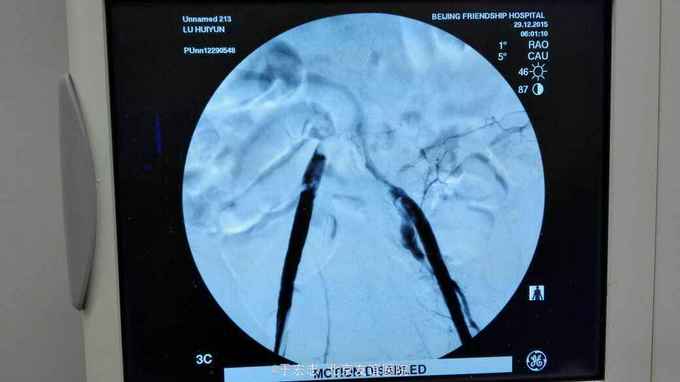

男性76岁,腹主动脉骑跨栓塞,经外院ct证实,病程3天,转至我院。

全腔内技术操作,用8F rotarex机械取栓导管操作,术前留置股静脉鞘,边操作边放静脉血,减少毒素吸收。静脉血经自体血回收处理。 操作完成后以血管缝合器缝合股动脉穿刺点,加压包扎。 患者转重症医学科途中出现心跳骤停,于手术室心外按压2小时复苏成功,转重症医学科血滤治疗。术后五小时生命体征均可维持,但家属还是放弃进一步治疗转运回当地治疗。